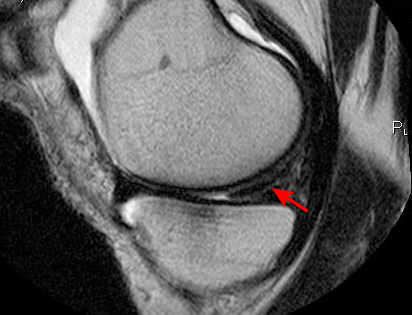

Considered the ideal imaging test for meniscal tear.[3][26][29]

Reported as 86.3% accurate for diagnosing a medial meniscus tear, and 88.8% accurate for diagnosing a lateral meniscal tear.[31]

Also useful for identifying associated ligament compromise and articular cartilage changes, and supporting pre-surgical planning if arthroscopy is indicated.[1][Figure caption and citation for the preceding image starts]: MRI scan demonstrating horizontal cleavage tear of medial meniscus (arrow); white horizontal line separates the inferior and superior portions of the torn meniscusFrom the collection of Dr Kevin R. Stone [Citation ends].

signal changes within meniscus on T1 and T2 images; sagittal views: anterior and posterior meniscal tears; coronal view: far medial and far lateral meniscal tears